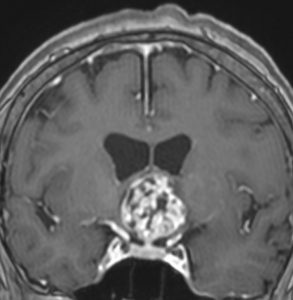

成人の第3脳室内部に局在する頭蓋咽頭腫です。経脳梁法で両側のモンロー孔から全摘出しました。下垂体組織は残っています。これは乳頭状頭蓋咽頭腫と呼ばれるもので,成人にしか発生しません,のう胞がなく石灰化もないのが大きな特徴です。境界が明瞭で柔らかく摘出が簡単なタイプとして知られています。この患者さんも術後に下垂体機能不全も視床下部障害も生じませんでした。

第3脳室内のadamantinomatous craniopharyngiomaです。これを両側前頭開頭,経脳梁法 transcallosall approachで摘出しました。下垂体と下垂体柄を温存するためです。

初回手術から6年後,原発部位に腫瘍はありません。しかし,前頭部大脳鎌(赤矢印)に腫瘍が発生しました。これは手術経路(緑の線)に沿った位置にあるので,drop metastasisだとわかりました。病理は初回と同じものです。このdrop metastasisは意外に多いものです。頭蓋咽頭腫は,極小の腫瘍片でも脳表や脳槽にこぼれ落ちれば,そこで着床して,数年後に再発となって現れるということを示しています。ですから,手術の時に断片を残したり落としたりしてはなりません。